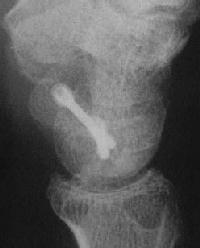

With intercalated iliac bone graft...

Click for larger image

and healing.